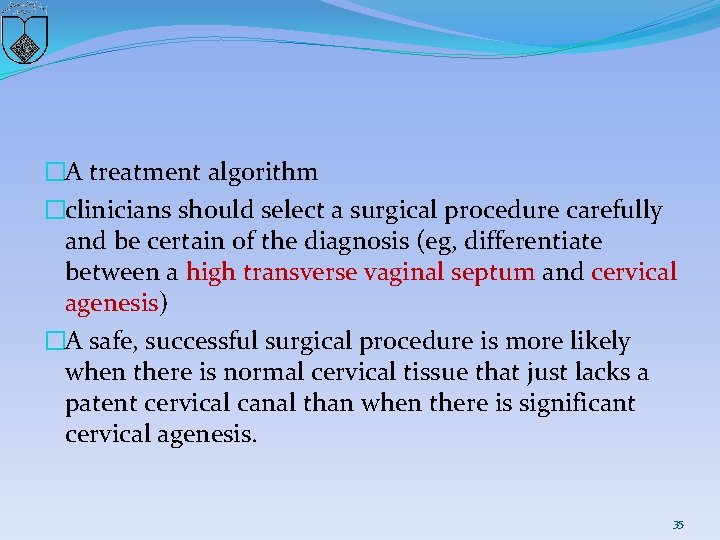

�A treatment algorithm �clinicians should select a surgical procedure carefully and be certain of the diagnosis (eg, differentiate between a high transverse vaginal septum and cervical agenesis) �A safe, successful surgical procedure is more likely when there is normal cervical tissue that just lacks a patent cervical canal than when there is significant cervical agenesis. 35